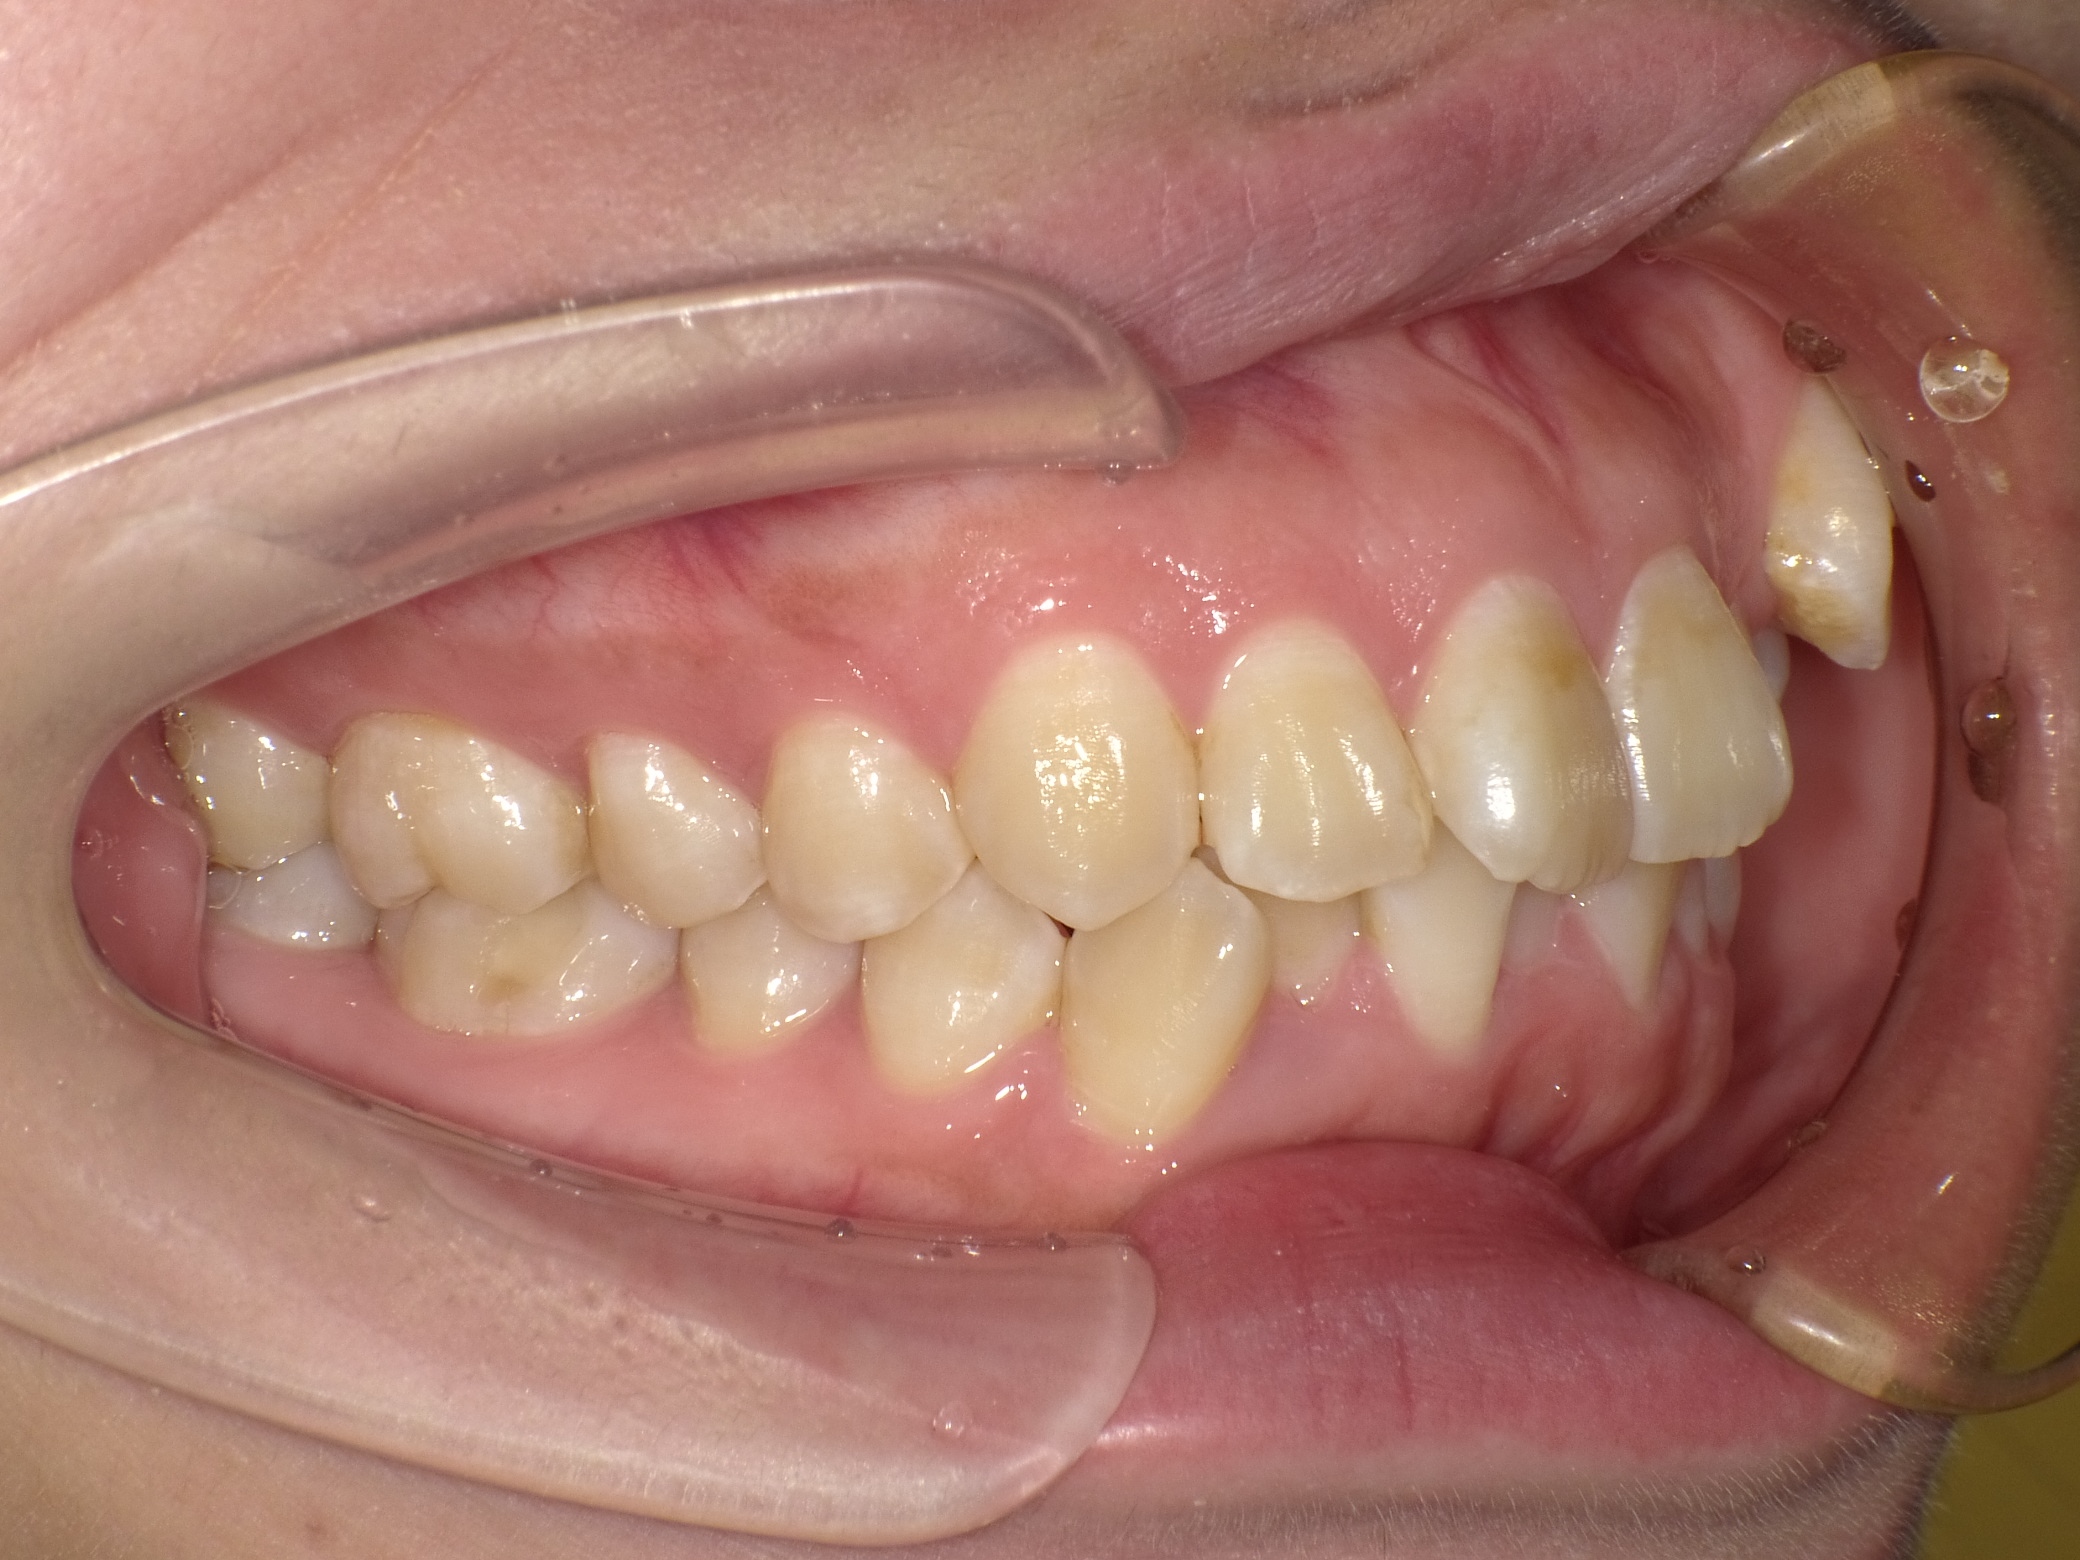

口内左

治療前

- ワイヤー矯正(抜歯を伴う) 上顎左側の犬歯が低位(上の方にあること)にあり、いわゆる八重歯の状態でした。 犬歯が本来入るべきスペースは完全に横の歯が寄ってしまっており、失われていた為、抜歯を行い配列としました。 正中を合わせるため、途中顎間ゴムを使用して最終の調整を行いました。